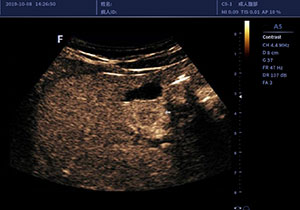

造影成像CONTRAST IMAGING

编码谐波造影成像